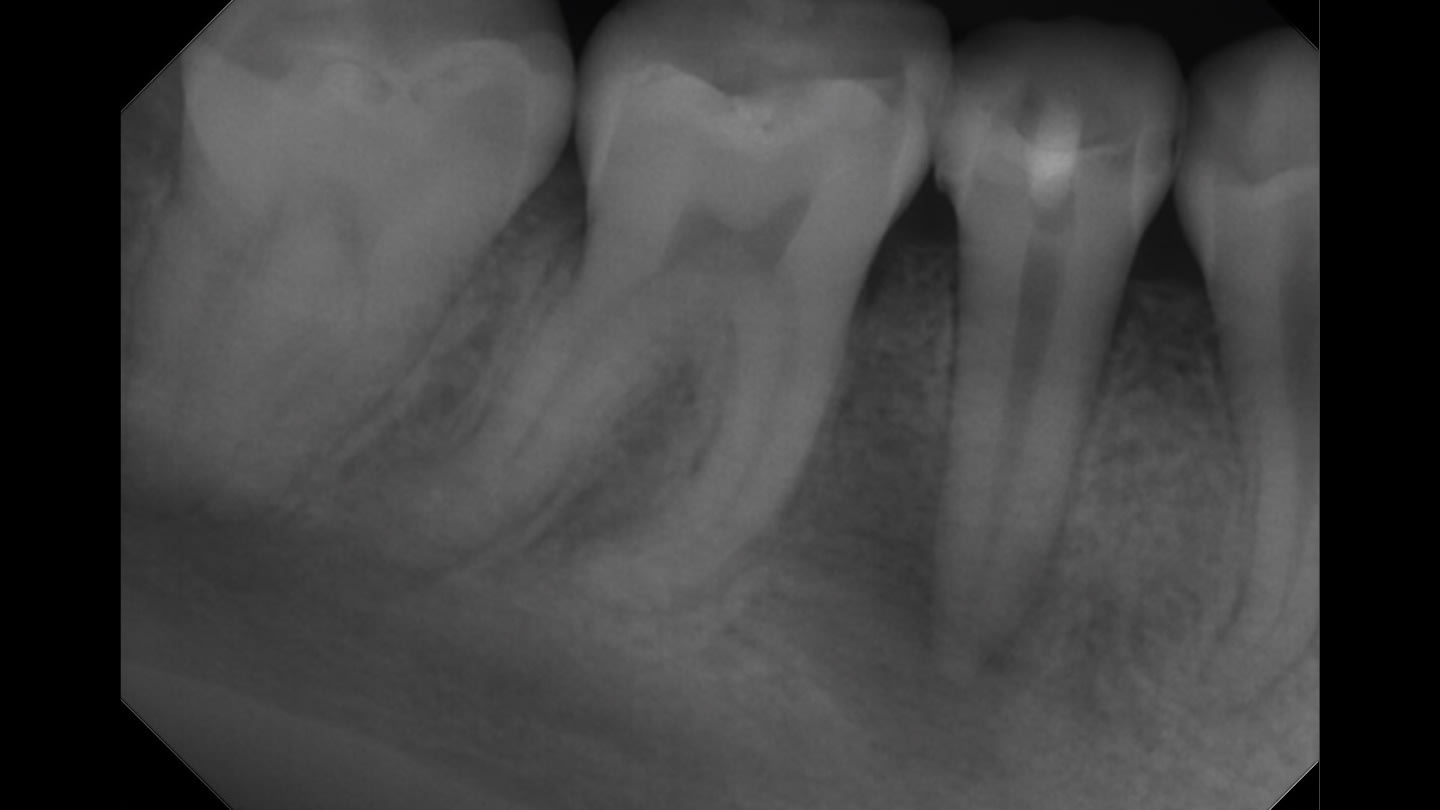

Dr. Kale primarily uses a single-cone obturation technique in single-visit cases, placing the sealer directly into the canal before seating the cone. Because the material forms a thin film and provides adequate working time, he finds that adjustments can be made when necessary without difficulty. “If you need to reposition or remove the cone before the sealer fully sets, it’s manageable,” he says. “That flexibility makes the procedure more predictable.”

Like many clinicians, Dr. Kale views the obturation stage as a critical determinant of long-term treatment success. While irrigation and shaping remove infected tissue and reduce bacterial load, an effective seal is necessary to prevent reinfection of the canal system. “You can perform a beautiful root canal, but if the seal is compromised, bacteria can eventually find their way back in,” he says. The high pH and bioceramic composition of EdgeUtopia Sealer contribute to antimicrobial activity and favorable healing conditions, which Dr. Kale believes can help improve clinical outcomes.

He also emphasizes the importance of maintaining a proper seal during the period between endodontic therapy and placement of the final restoration. In some cases, patients may delay receiving a crown or other definitive restoration, creating the potential for microleakage if the canal system is not adequately sealed. “The material’s low solubility and biocompatibility help provide reassurance that the seal will remain stable during that time,” Dr. Kale says.